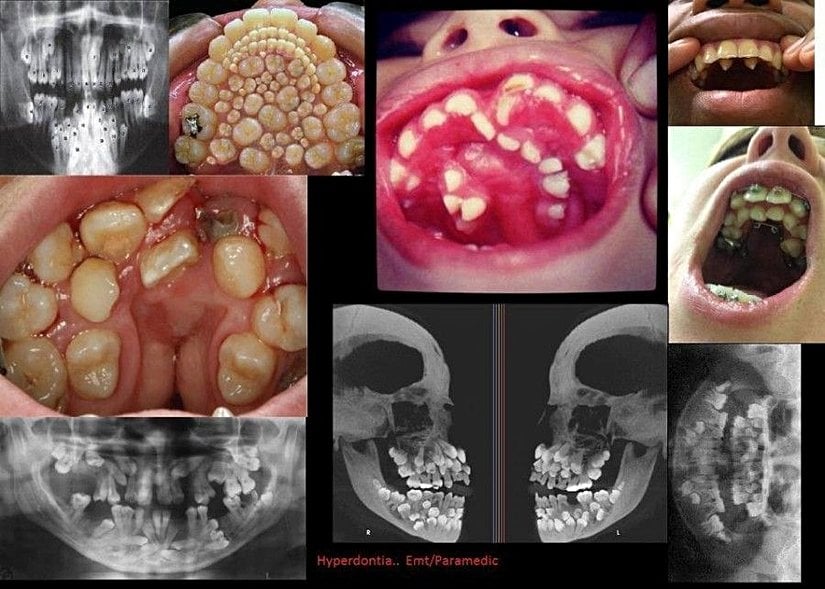

Hiperdontia birçok farklı formda karşımıza çıkar. En yaygın olarak görüneni ise meziyoden olarak bilinen, önde bulunan iki kesici dişimiz arasında ekstra dişlerin bulunmasıdır. Sonrasında ise fazladan öğütücü dişlerin bulunması, paramolar dişlerin bulunması (kesici ve öğütücü dişler arasında ekstra dişlerin gelişmesi), alt çene ön öğütücü dişlerin sayısının fazla olması, köpek dişlerinin sayısının fazla olması, vb. diş sayısı artışları gelir.

Fotoğrafta da gösterildiği gibi, birçok farklı hiperdonti türü bilinmektedir. Bunlardan sol üst köşede 2. sırada bulunan ve tüm damağın dişlerle kaplandığını gösteren fotoğraf sahtedir ve Photoshop ile üretilmiştir; dikkatli bakıldığında kendini tekrar eden dişlerin olduğu görülecektir. Ancak diğerleri gerçektir ve tıbben görülen hiperdonti vakalarına örnekler teşkil etmektedir.